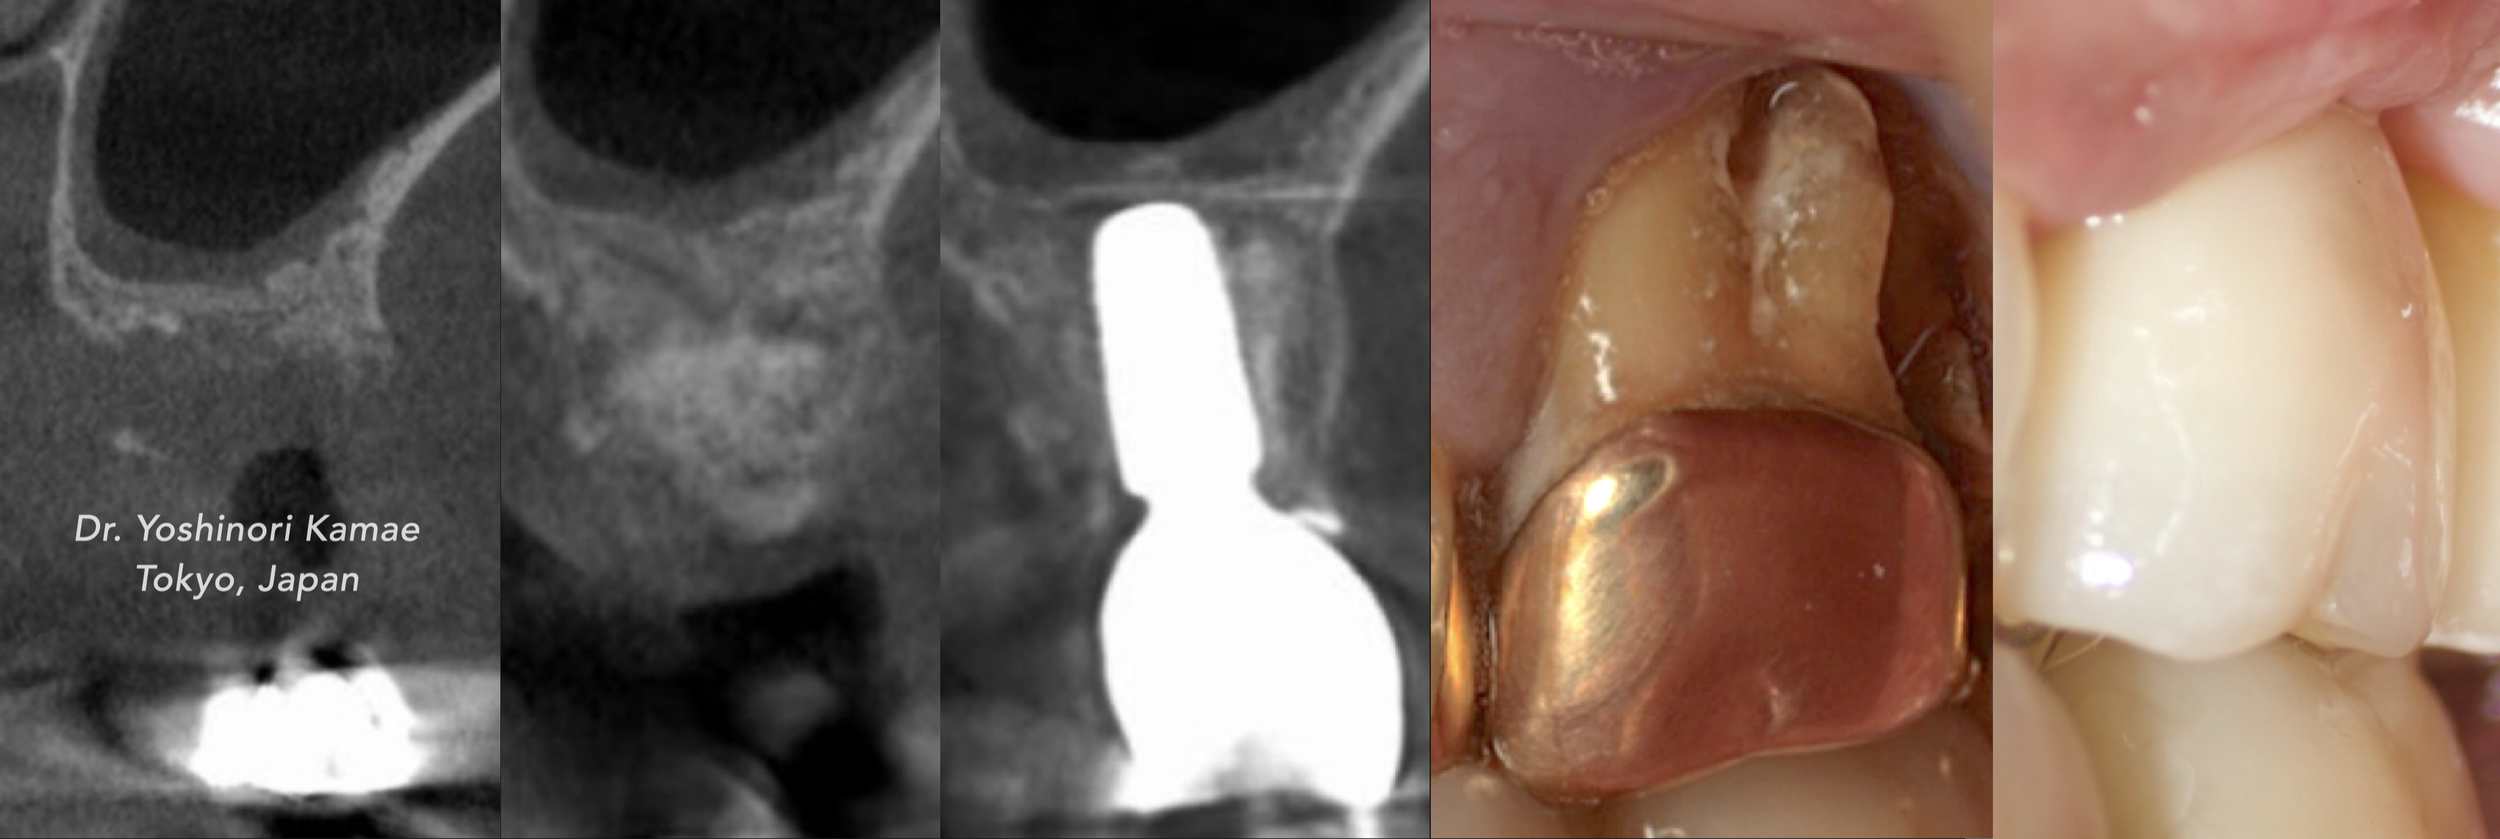

CASE 3. VERTICAL AUGMENTATION